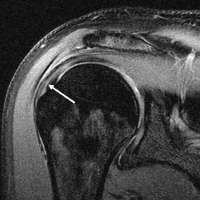

Diagnostic modalities, dependent on circumstances, include X-ray, MRI, MR arthrography, double-contrast arthrography, and ultrasound. Although MR arthrography is currently considered the gold standard, ultrasound may be most cost-effective.[16] Usually, a tear will be undetected by X-ray, although bone spurs, which can impinge upon the rotator cuff tendons, may be visible.[17] Such spurs suggest chronic severe rotator cuff disease. Double-contrast arthrography involves injecting contrast dye into the shoulder joint to detect leakage out of the injured rotator cuff[18] and its value is influenced by the experience of the operator. The most common diagnostic tool is magnetic resonance imaging (MRI), which can sometimes indicate the size of the tear, as well as its location within the tendon. Furthermore, MRI enables the detection or exclusion of complete rotator cuff tears with reasonable accuracy and is also suitable to diagnose other pathologies of the shoulder joint.[19]

MRI

Magnetic resonance imaging (MRI) and ultrasound[27] are comparable in efficacy and helpful in diagnosis although both have a false positive rate of 15 - 20%.[28] MRI can reliably detect most full-thickness tears although very small pinpoint tears may be missed. In such situations, an MRI combined with an injection of contrast material, an MR-arthrogram, may help to confirm the diagnosis. It should be realized that a normal MRI cannot fully rule out a small tear (a false negative) while partial-thickness tears are not as reliably detected.[29] While MRI is sensitive in identifying tendon degeneration (tendinopathy), it may not reliably distinguish between a degenerative tendon and a partially torn tendon. Again, magnetic resonance arthrography can improve the differentiation.[29] An overall sensitivity of 91% (9% false negative rate) has been reported indicating that magnetic resonance arthrography is reliable in the detection of partial-thickness rotator cuff tears.[29] However, its routine use is not advised, since it involves entering the joint with a needle with potential risk of infection. Consequently, the test is reserved for cases in which the diagnosis remains unclear.